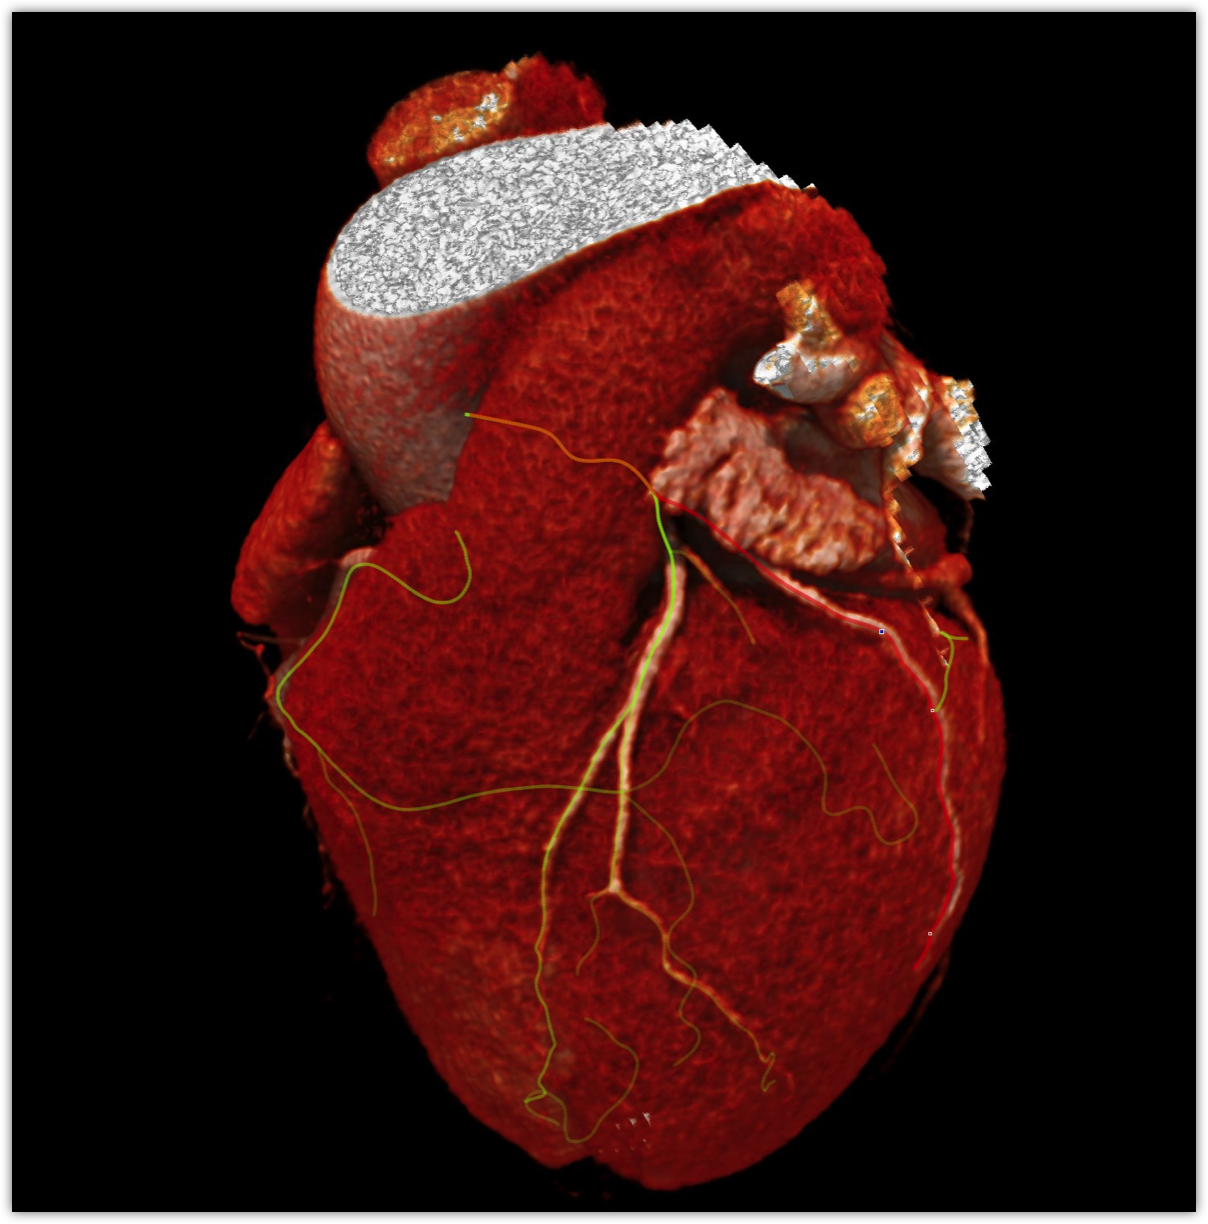

We believe in keeping you as healthy as possible. One of the ways we do this is by checking for heart disease with a Coronary CT Angiogram (CCTA) — a non-invasive scan that can see disease in your heart vessels even if you have no symptoms.

Most people have no symptoms until it’s too late. A Coronary CT Angiogram (CCTA) lets us see disease in the vessels of your heart — before a heart attack happens.

Right coronary scan